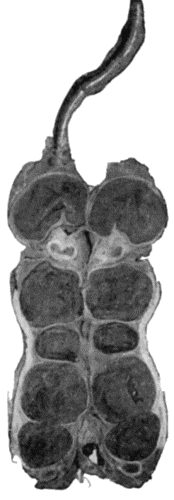

135.Cadaver, illustrating the alterations in the Lower Limbs resulting from Ostitis Deformans 475

40.Ulcerating Gumma of Lips 169